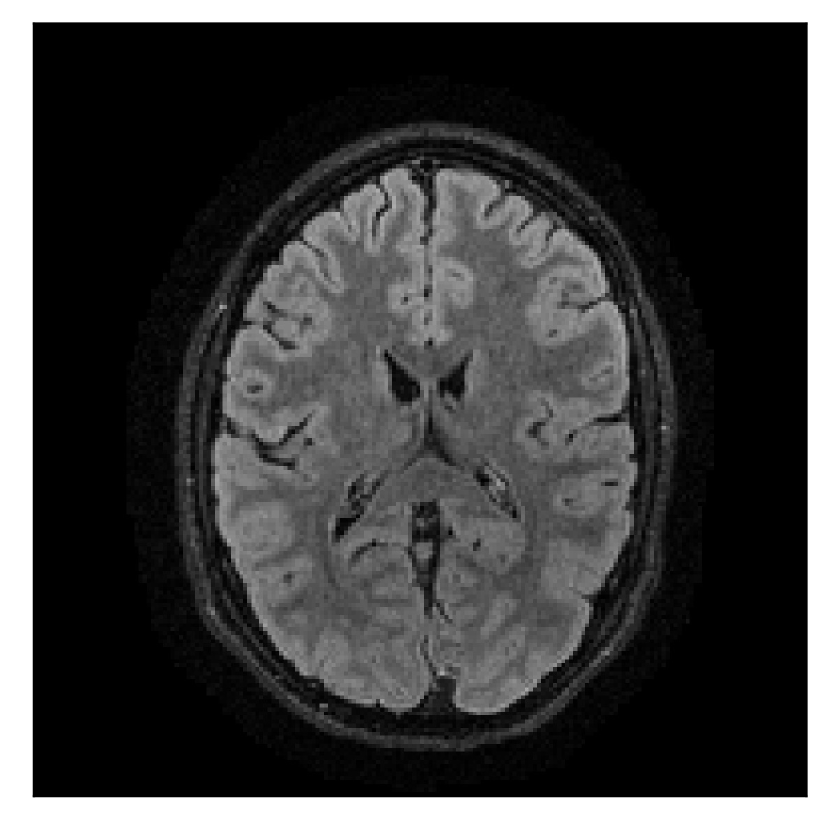

4.2 Experiment 2: choice of the reference contrast

With the experiment described in Section 3.2, we demonstrate the flexibility of the correction scheme with respect to the choice of the reference contrast. The results are shown in Figure 10. Contrary to the experiments detailed in the previous section, we are now considering a T2-weighted reference contrast to guide the correction of a T1-weighted corrupted contrast. The quality of the correction indicates that the proposed technique is rather flexible in terms of reference contrast.

| Section 3.2, Figure 10 | Sagittal | 25.84 | 28.07 | 0.7032 | 0.8093 |

| Coronal | 26.35 | 30.40 | 0.7851 | 0.9021 | |

| Axial | 28.11 | 30.54 | 0.8248 | 0.9012 | |

| Section 3.2, Figure 10 | T1 | Completely corrected | Some blurring | No additional artifacts | Good grey white matter differentiation, |

| some loss of grey matter low signal | |||||